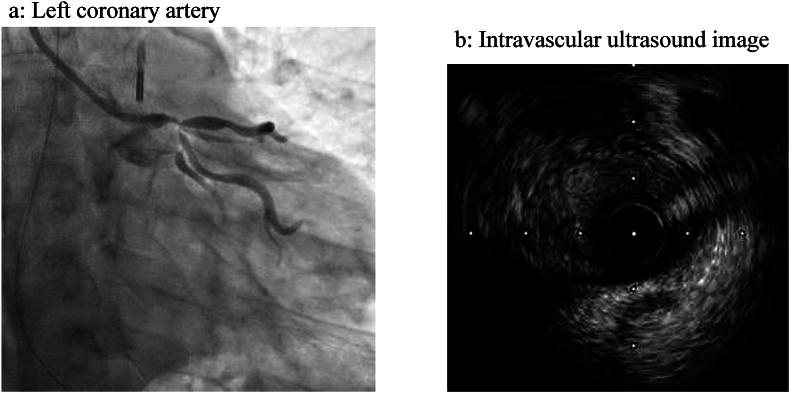

Abstract Image